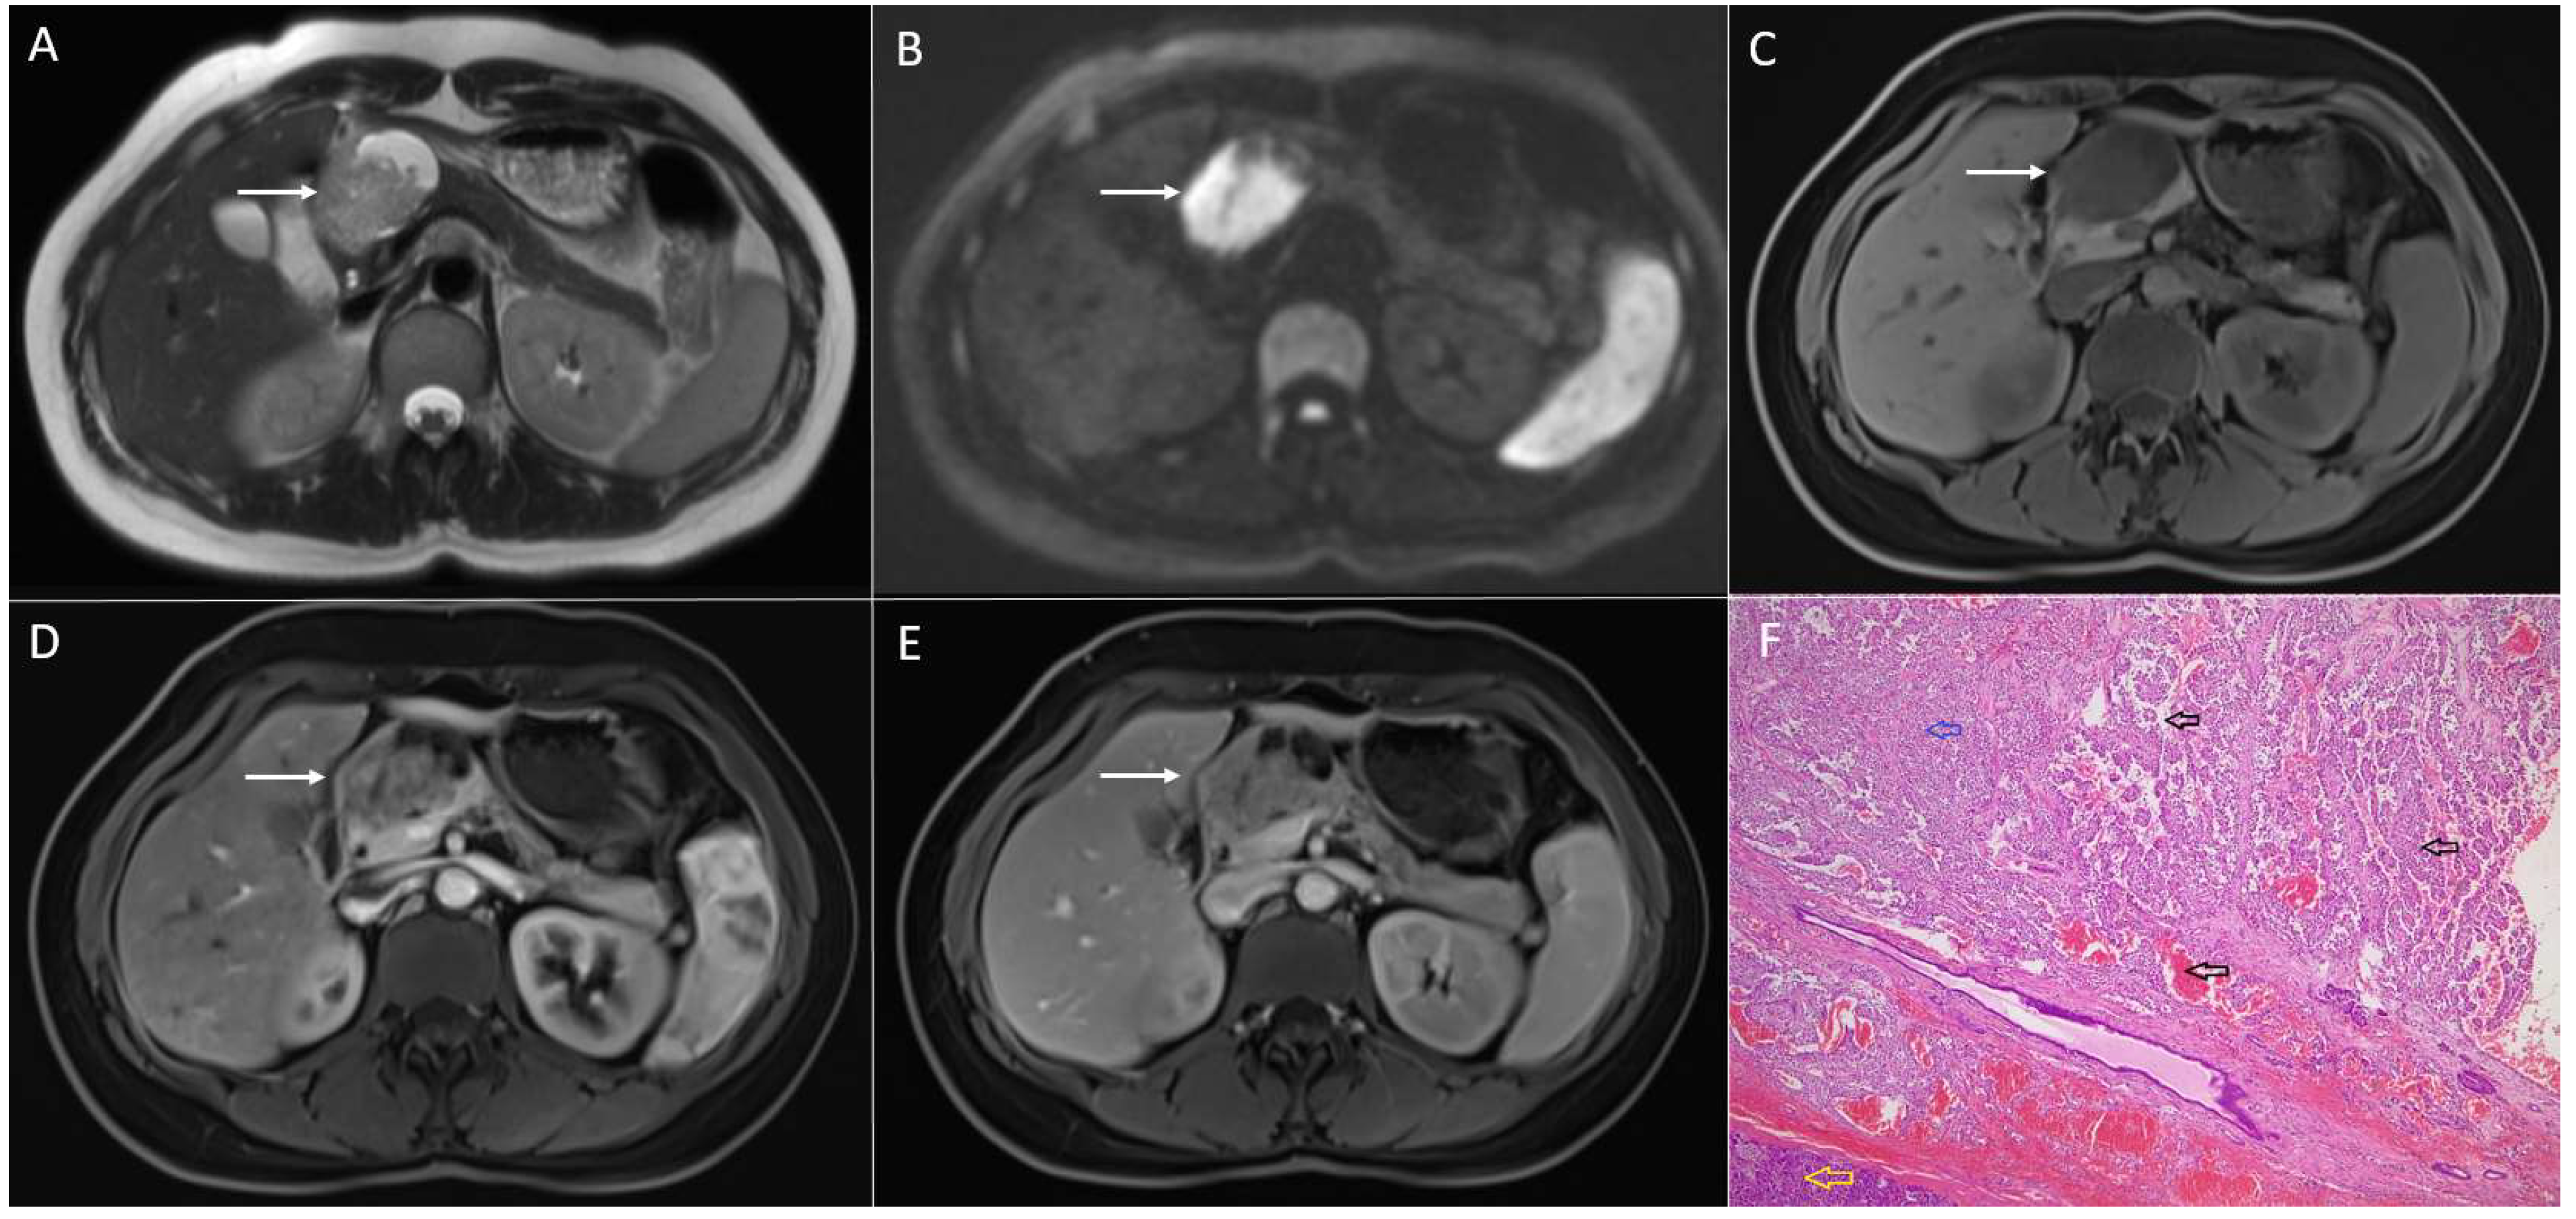

2. Typical Imaging Presentation of Solid Pseudopapillary Neoplasms

3.1. Neuroendocrine Tumors